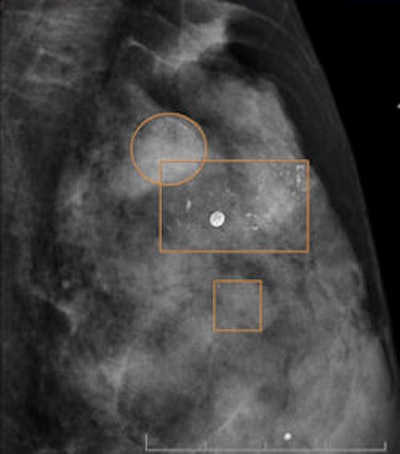

A 57-year-old woman with invasive ductal carcinoma 18 mm in size. CAD rectangles indicate calcifications. In the upper outer quadrant of the left breast, an architectural distortion not detected by CAD can be seen.Now standard protocol

A 58-year-old woman with in-situ ductal carcinoma 29 mm in size. Immunohistochemical staining demonstrated focus of microinfiltration (1 mm). In digital mammography, some pleomorphic calcifications correctly depicted by CAD can be seen.Other institutions could adopt the practice as well, provided they have historical annual audits to be able to know which readers could be selected to read with CAD. "The appropriate selection of radiologists is vital in order to reach a good cancer detection rate," he added.